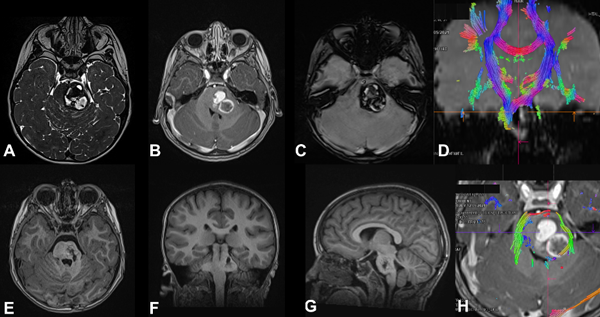

Figura 3. MC cerebral infratentorial del tronco del encéfalo. Paciente masculino de 5 años que ingresa por síndrome cerebeloso, asociado a hemiparesia faciobraquiocrural izquierda. Evoluciona favorablemente, egreso hospitalario. A los 2 meses reingresa por un episodio de resangrado. Se decide cirugía programada. A) RM T2 FIESTA que muestra lesión protuberancial, heterogénea, con halo hipointenso. B) RM T1 con contraste EV que muestra sangrado en distintos estadios. C) RM SWI imagen típica. D) y H) RM DTI-tractografía que muestra tractos pontinos transversos en rojo y pedúnculo cerebeloso medio en verde, en este caso se eligió un abordaje supracerebeloso infratentorial lateral y se accedió al cavernoma a través del surco mesencefálico lateral. E-G) RM postquirúrgica de cerebro secuencia T1 en los 3 planos, se evidencia la resección completa de la lesión.

Figura 4. Cavernoma del tronco del encéfalo. Paciente masculino de 11 años, antecedentes de cirugía de resección parcial del cavernoma en dos oportunidades e hidrocefalia que requirió sistema de derivación ventriculoperitoneal. Ingresó por déficit neurológico focal progresivo que agregó trastornos deglutorios, episodios de apneas y paro cardiorrespiratorio, por lo que se realizó la revisión valvular, sin mejoría, para luego efectuar cirugía de resección del cavernoma. Resección completa. Paciente evoluciona favorablemente recuperando función respiratoria y parcial del déficit motor. A) TC de cerebro de urgencia sin contraste que muestra sangrado bulboprotuberancial extenso. B) RM postoperatoria de cerebro con contraste EV, corte coronal, lecho quirúrgico libre de lesión. C) Corte sagital del mismo estudio, nótese el trayecto de disección, generando imagen de tronco “atravesado”.

De acuerdo con la bibliografía, entre el 10 y el 23% de las MC se encuentra a nivel de la fosa posterior, predominantemente en la región de la protuberancia, pudiendo encontrarse en hemisferios cerebelosos o en el resto del tronco del encéfalo. En nuestra serie obtuvimos resultados similares, con 30% de las lesiones de ubicación infratentorial, siendo dos tercios de ellas a nivel del tronco cerebral (ver Figuras 3 y 4).3,5,18,24,25,34

Dos de los tres casos que presentamos requirieron tratamiento quirúrgico (ver Figuras 3 a 5) debido al déficit neurológico progresivo que interfería con la calidad de vida y al efecto de masa con desplazamiento de las estructuras bulboprotuberanciales circundantes. Ambos casos presentaron mejoría sintomática postquirúrgica, con recuperación parcial del foco neurológico, sin nuevos déficits asociados al procedimiento.